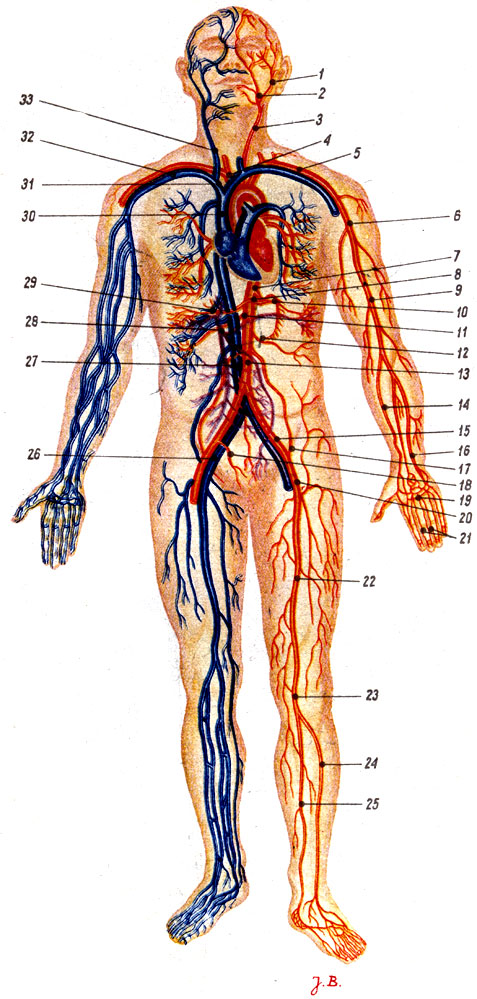

Анатомия человека: кровеносная система и её связь со скелетом